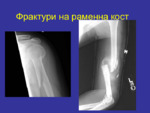

Фрактури на раменна кост

Фрактура – нарушаване целостта на дадена кост в различни оси. Видове фрактури...